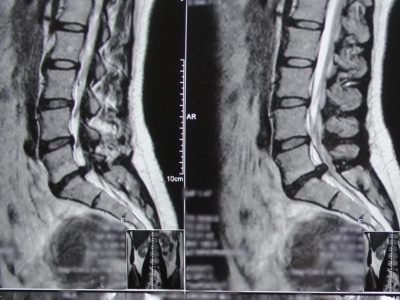

Лишний вес провоцирует проблемы с позвоночником. Но бывают и нетипичные ситуации - недавно в нейрохирургическое отделение поступила худенькая молодая женщина с огромной грыжей межпозвоночного диска. Она уже почти не могла нормально ходить, сидеть, лежать... Жизнь свелась к нулю - только боль.

Обычно к грыже межпозвоночного диска приводят малоподвижный образ жизни, большой вес, большая не физиологичная нагрузка на позвоночник, наследственность (врожденная слабость соединительных тканей), старение диска (он теряет влагу, перестает выполнять функцию амортизатора и выпадает в просвет позвоночного канала), - рассказывает врач-нейрохирург Нина Николаевна Вознесенская @voznesenskai_neirohirurg - У нашей пациентки фактор лишнего веса полностью отсутствует, а вот другие моменты есть».

Пациентке провели эндоскопическое удаление грыжи диска (эндоскопическая микродискэктомия). Это операция под общим наркозом или спинальной анестезией с помощью эндоскопа диаметром 4 мм, специальных миниатюрных инструментов под визуальным контролем на экране дисплея. Операция проводится через миниатюрный прокол мягких тканей, что сокращает риск осложнений и существенно уменьшает послеоперационный реабилитационный период.

Цель операции - высвобождение нервного корешка, - продолжает Нина Николаевна. - Мы удалили выпавший фрагмент грыжи и наложили один миниатюрный шов. И все. Послеоперационных болей практически нет - ткани не повреждены. Вставать и ходить можно в первый день, а на следующий день отправляться домой».